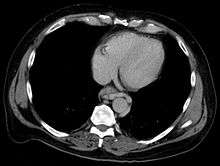

In medicine (gastroenterology), esophageal varices (or oesophageal varices) are extremely dilated sub-mucosal veins in the lower third[1] of the esophagus. They are most often a consequence of portal hypertension, commonly due to cirrhosis; patients with esophageal varices have a strong tendency to develop bleeding.

Normal portal pressure is approximately 9 mmHg compared to an inferior vena cava pressure of 2–6 mmHg. This creates a normal pressure gradient of 3–7 mmHg. If the portal pressure rises above 12 mmHg, this gradient rises to 7–10 mmHg.[3] A gradient greater than 5 mmHg is considered portal hypertension. At gradients greater than 10 mmHg, blood flow through the hepatic portal system is redirected from the liver into areas with lower venous pressures. This means that collateral circulation develops in the lower esophagus, abdominal wall, stomach, and rectum. The small blood vessels in these areas become distended, becoming more thin-walled, and appear as varicosities.

In situations where portal pressures increase, such as with cirrhosis, there is dilation of veins in the anastomosis, leading to esophageal varices. Splenic vein thrombosis is a rare condition that causes esophageal varices without a raised portal pressure. Splenectomy can cure the variceal bleeding due to splenic vein thrombosis.